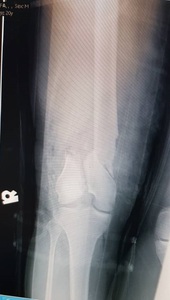

A 22-year-old man presented to our hospital in December 2020 following a motor vehicle accident. The patient had no significant medical, family, or allergy history. He worked in a metal factory and occasionally smoked. The sustained injuries included a closed fracture of the right neck of the femur, an open right supracondylar femur fracture (Gustilo 3C), and an open midshaft fracture of the right tibia (Gustilo 2) (Figures 1, 2, and 3).

Initial management involved screw fixation of the femoral neck, wound debridement of the right thigh, and placement of an external fixator across the right knee (Figures 4 and 5), followed by a one-week course of intravenous cefuroxime. By January 2021, the right leg had become gangrenous and deemed nonviable. Right above-knee amputation (AKA) with adductor myodesis was performed, followed by intravenous cefuroxime for another week.